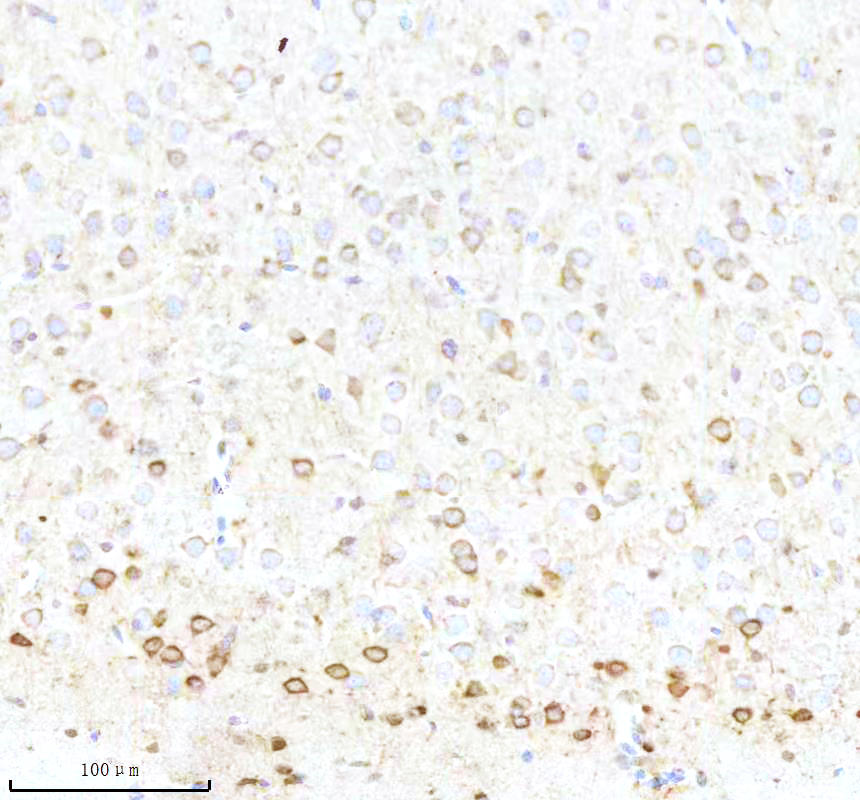

IHC analysis of BNIP3L using anti-BNIP3L antibody (BM5174) .

BNIP3L was detected in a paraffin-embedded section of mouse brain tissue. The tissue section was incubated with rabbit anti-BNIP3L Antibody (BM5174) at a dilution of 1:200 and developed using HRP Conjugated Rabbit IgG Super Vision Assay Kit (Catalog # SV0002) with DAB (Catalog # AR1027) as the chromogen.

IHC analysis of BNIP3L using anti-BNIP3L antibody (BM5174) .

BNIP3L was detected in a paraffin-embedded section of mouse brain tissue. The tissue section was incubated with rabbit anti-BNIP3L Antibody (BM5174) at a dilution of 1:200 and developed using HRP Conjugated Rabbit IgG Super Vision Assay Kit (Catalog # SV0002) with DAB (Catalog # AR1027) as the chromogen.